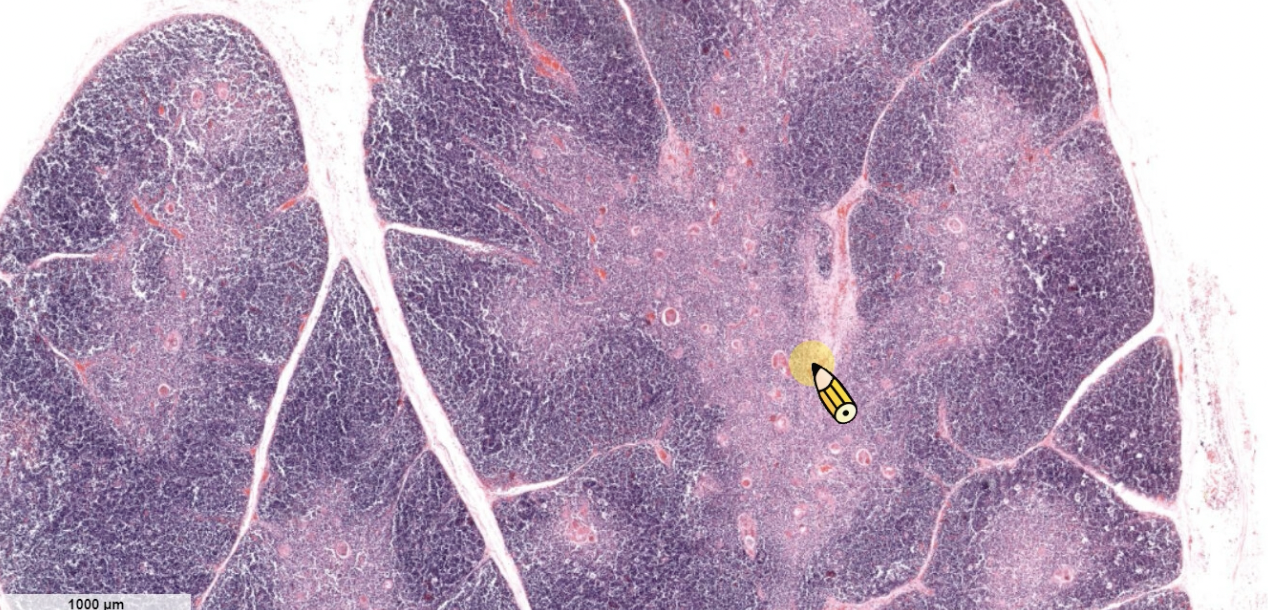

- fibrous capsule>trabeculae

- reticular fiber

- white pulp( Secondary lymphatic nodule)

- red pulp (other)

- central a. 被 T cell 包覆(Periarterial lymphatic sheath)

- Secondary lymphatic nodule

Central artery